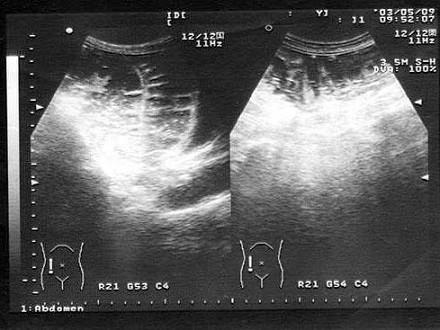

问题 男,6岁,阵发性腹痛,呕吐数小时就诊。PE:肠鸣音亢进,呈气过水音。根据超声声像图诊断为?(?)

选项 A.急性肠梗阻 B.急性肠炎 C.肠套叠 D.肠穿孔 E.胃癌

答案 A